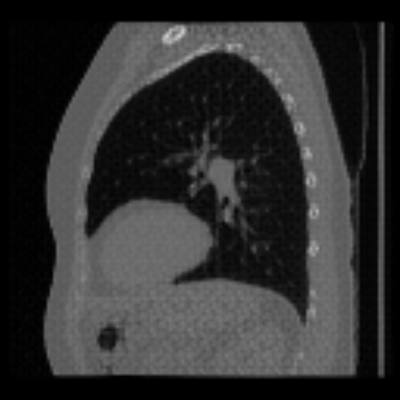

| Axial | Coronal | Sagittal | |

| X2CTGAN | ![]() |

![]() |

|

| DX2CT | ![]() |

| Ground-truth | ![]() |

Figure 3 and Table I(a) using biplanar X-rays show that proposed DX2CT can outperform three existing SOTA methods. Figure 3 shows that DX2CT can provide more accurate overall shapes and details compared to the existing methods. The quality of reconstructed CT slices in the axial plane is less satisfactory than those in the other planes. The reason is that the axial plane is perpendicular to the planes of biplanar X-rays so there exists less spatial (i.e., depth) information in the axial plane. Without using the perceptual loss [33], proposed DX2CT gave comparable LPIPS results with PerX2CTs using [33] in training. Compare their LPIPS results in Table I(a).